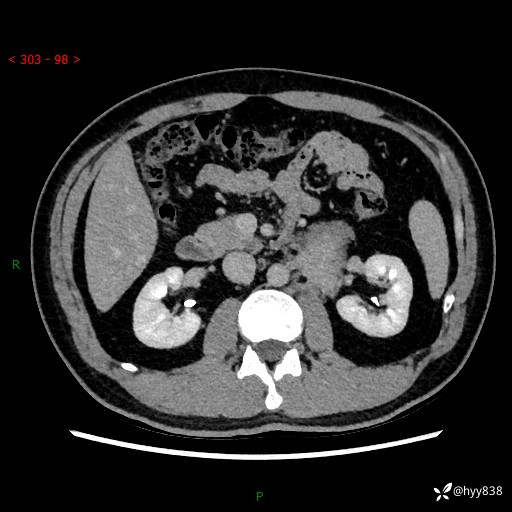

现病史:患者3月余前检查发现左侧腹膜后占位,大小约3.7*4.9cm,平素无腰疼,无肉眼血尿,无尿频尿急等不适,当时未特殊处理,在门诊复查CT提示左侧腹膜后占位,门诊拟“左侧腹膜后占位”收入院。 起病以来,患者精神佳,饮食、睡眠良好,大小便正常,体力体重无明显变化。

腹膜后CT平扫+增强